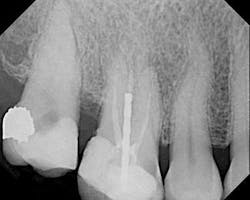

The female patient whose radiographic image appears in Figure 1 presented with a clinical history that is instructive with regard to endodontic diagnosis, treatment planning, and emergency management.

Among other findings, No. 3 was sensitive to percussion and palpation. The tooth was not mobile and probing was approximately a six at the distal. The tooth had never been crowned. There was significant uncleaned and unfilled space in the root canal system, especially in the palatal and mesiobuccal roots. Recurrent decay was present at the mesial.

No. 2 had an access made through the occlusal and no discernable canals were visible in this or any of the radiographic angles. No. 2 was asymptomatic upon my examination. The patient’s medical history was noncontributory.

3) There was no evidence of vertical root fracture on No. 3. That said, whenever bone loss is present around a post and endodontically treated tooth, the real possibility of vertical fracture must be ruled out. A fistula, swelling, furcal bone loss, advanced mobility, and vertical probing defect disproportionate to other probings on the tooth are all indications of a vertical root fracture.